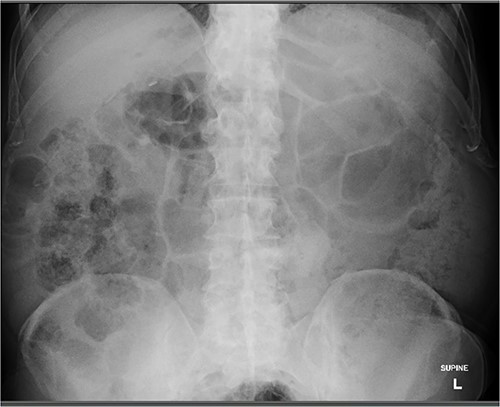

An 80 year old male presented to the emergency department after accidentally swallowing his hearing aids. On presentation he was pain free, hemodynamically stable, and had a soft abdomen. He had a background of type-2 diabetes, rheumatoid arthritis and diverticulitis. The hearing aids were powered by lithium battery. X-ray found two foreign bodies in the left upper abdomen (Fig. 1). After assessment in the emergency department, he returned home to await their natural passage. One hearing aid was found in his stools the following day, but he represented three weeks later as the second hearing aid remained unaccounted for. He underwent repeat abdominal x-ray and CT, which found the hearing aid retained within a presumed distal duodenal diverticulum (Figs 2 and 3). He was booked a push enteroscopy the following day.

Abdominal CT identifying one hearing aid in a jejunal diverticulum 3 weeks after initial presentation – axial view.